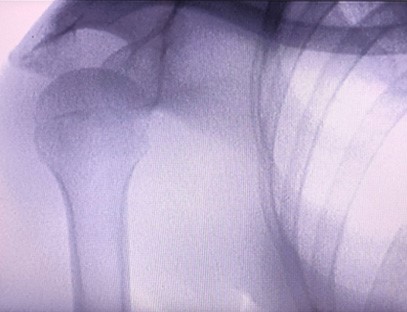

Una máquina de rayos X portátiles un instrumento portátil de baja dosis de radiación, muy seguro, que puede obtener imágenes de alta calidad al tiempo que reduce la exposición a la radiación. Compensa las deficiencias de los grandes equipos hospitalarios y se puede mover y transportar en cualquier momento. Especialmente adecuado para unidades e individuos con presupuesto insuficiente y bajos requisitos de imágenes. Nuestra máquina de rayos X de nueva generación está equipada con una pantalla grande de alta definición de 10 pulgadas, que tiene un rango de ángulo de visión más amplio y puede ver completamente a través de toda la palma, incluidas fracturas, dislocaciones, artritis y tumores óseos. Se puede conectar a una impresora de películas para imprimir películas ortopédicas y también se puede utilizar para producción y pruebas industriales. No necesita un cuarto oscuro, perspectiva directa, observación en tiempo real. Esta máquina tiene un sistema de imágenes de alta resolución que puede capturar imágenes de cualquier estructura ósea con mucha claridad. Proporcionar los mejores equipos y soluciones de prueba de rayos X para fabricantes de productos médicos, de mascotas, industriales, electrónicos, departamentos de inspección y mantenimiento y laboratorios de investigación.

Especialización:Diseñado para las necesidades de las clínicas ortopédicas, especialmente adecuado paraImágenes de rayos Xde extremidades como manos, muñecas, codos, hombros, rodillas, tobillos, etc.

Imágenes claras:Se utiliza tecnología avanzada de imágenes digitales para proporcionar imágenes de rayos X de alta calidad, lo que ayuda a los médicos a diagnosticar la afección con precisión.